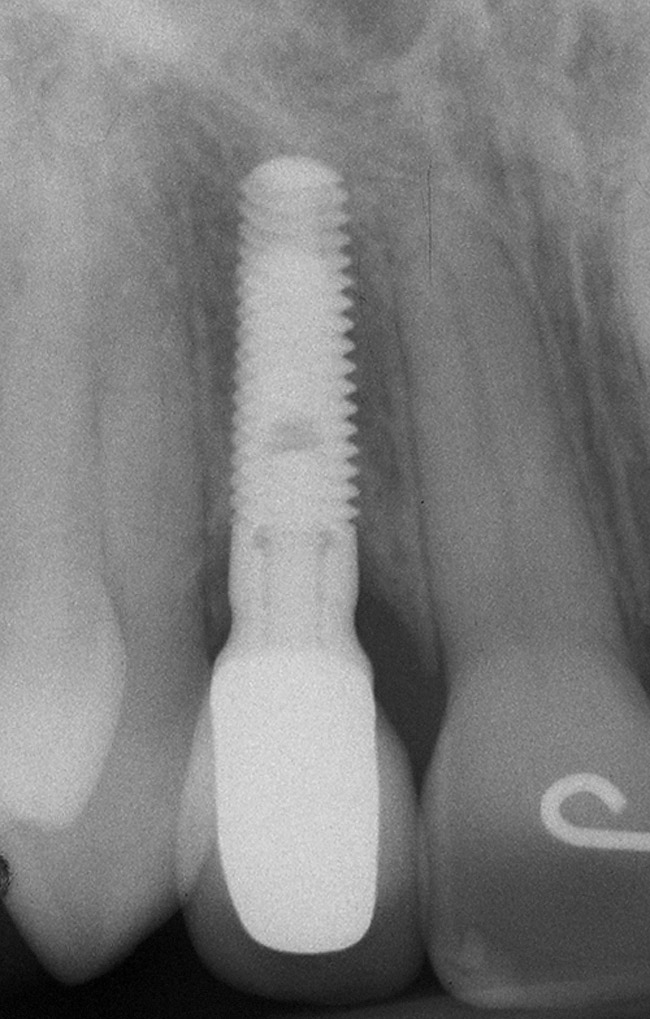

Figure 6d Completed treatment: revised RCT, zirconium post/pressed ceramic core cemented with Panavia 21¬Æ Resin Cement (Kuraray Dental). All-ceramic full-coverage crown cemented with Kerr NX3 Nexus¬Æ Third Generation Dual Cure Resin cement. Implant therapy not indicated.

Figure 6d

Figure 6e  Completed treatment: revised RCT, zirconium post/pressed ceramic core cemented with Panavia 21¬Æ Resin Cement (Kuraray Dental). All-ceramic full-coverage crown cemented with Kerr NX3 Nexus¬Æ Third Generation Dual Cure Resin cement. Implant therapy not indicated.

Figure 6e

Figure 6f  Completed treatment: revised RCT, zirconium post/pressed ceramic core cemented with Panavia 21¬Æ Resin Cement (Kuraray Dental). All-ceramic full-coverage crown cemented with Kerr NX3 Nexus¬Æ Third Generation Dual Cure Resin cement. Implant therapy not indicated.

Figure 6f